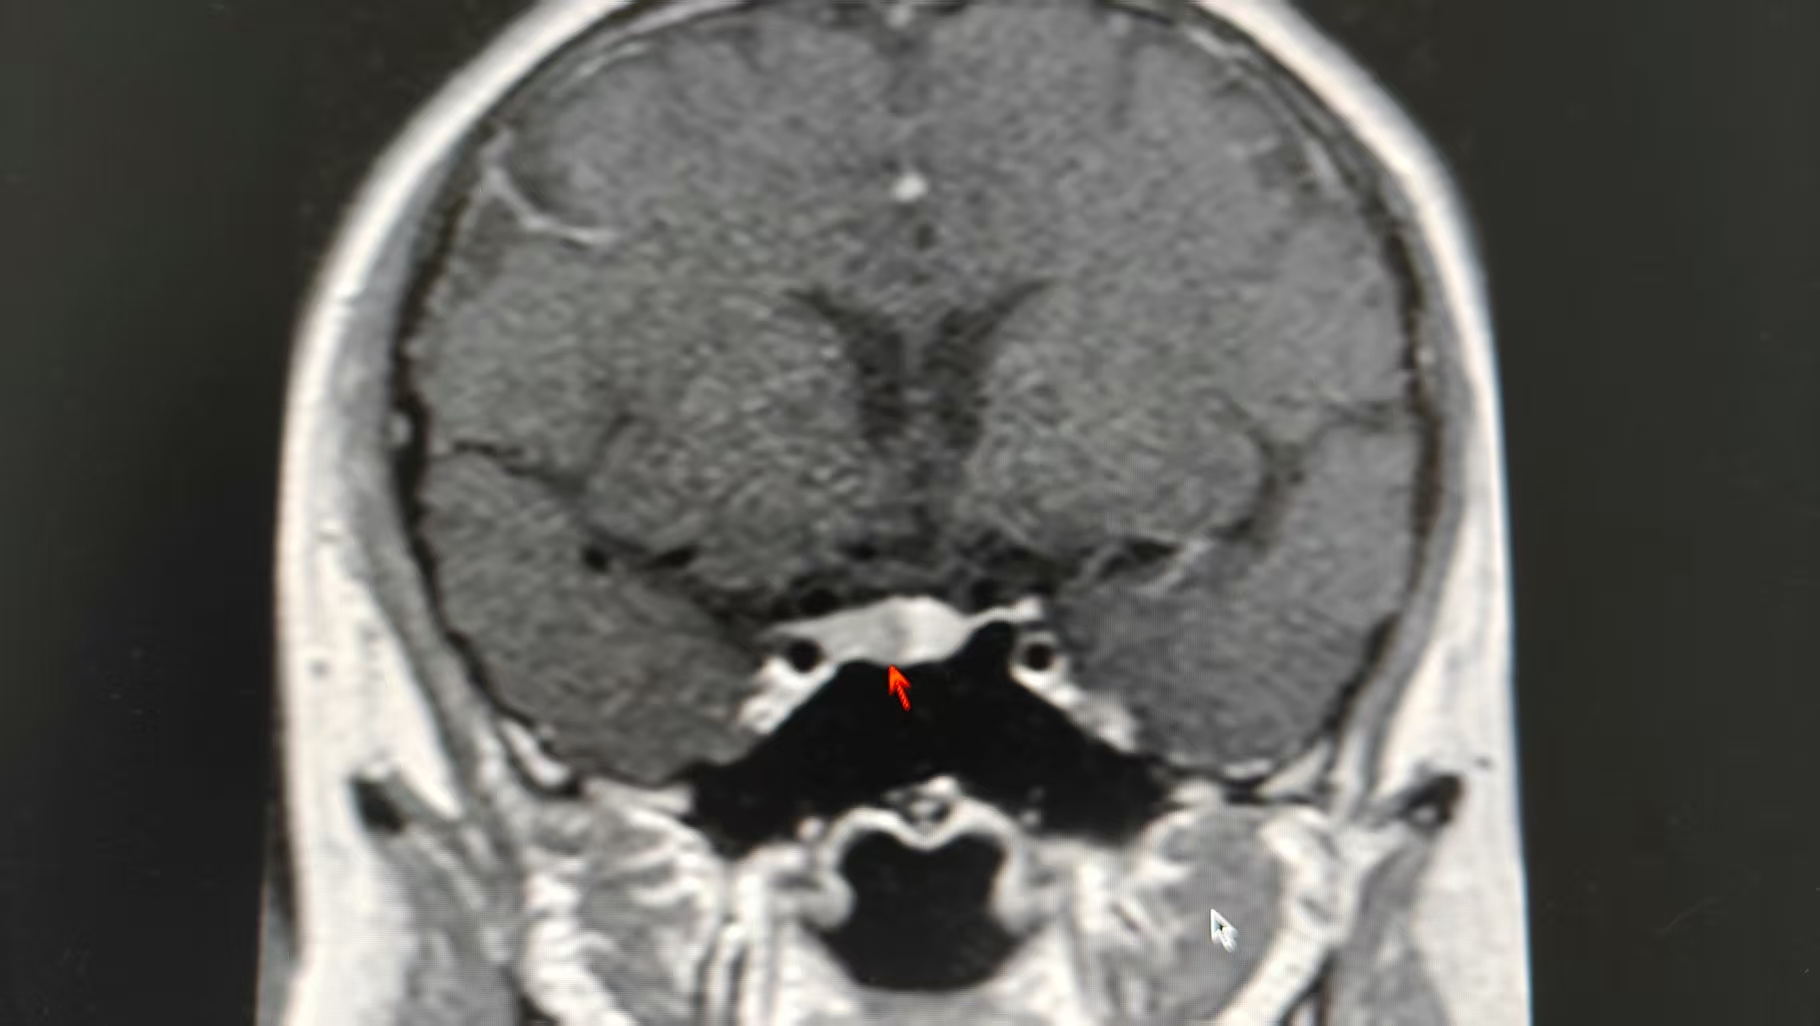

(▲箭头位置为李女士脑部垂体瘤。)

为查清病因,李女士住院治疗,王敏主任医师带领医疗团队开始了缜密的诊断过程,最终诊断指向ACTH依赖性库欣综合征——垂体ACTH瘤,该病的患者因ACTH过度分泌引发皮质醇增多症,典型症状包括向心性肥胖、满月脸、皮肤紫纹及代谢异常,可合并糖尿病、性腺功能抑制等并发症。由于肿瘤体积微小(通常直径毫米),CT及MRI(核磁共振)检出率较低,诊断主要依赖内分泌学检查。